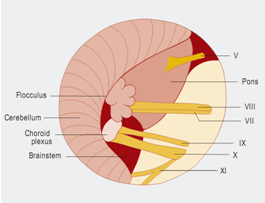

Figure 5小脑桥脑角区解剖示意图:Ⅴ=三叉神经;Ⅷ=蜗神经;Ⅶ=面神经;Ⅸ=舌咽神经;Ⅹ=迷走神经;Ⅺ=脊附属神经。